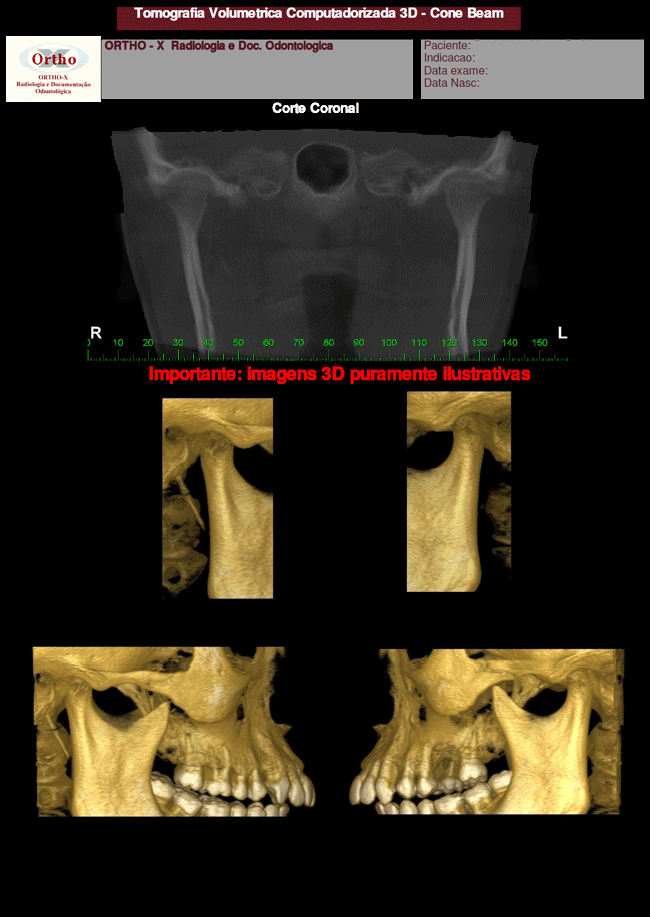

Exemplo de Exames: ATM